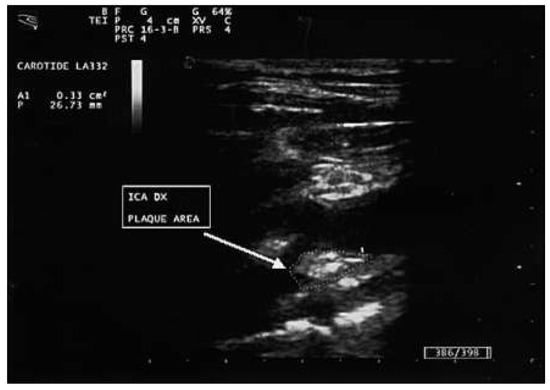

Carotid Ultrasonography in the Assessment of Cardiovascular Risk

by Aldo Pende, Nathan Artom, Giovanni Pistocchi, Livia Pisciotta and Franco Dallegri

Cardiovasc. Med. 2015, 18(2), 61; https://doi.org/10.4414/cvm.2015.00309 - 18 Feb 2015

Carotid ultrasound is one of the most accessible examinations in daily clinical practice for the evaluation of the arterial status. However, the clinical implications of the presence, the extension and the morphology of carotid damage are not entirely clear. Aim of this narrative [...] Read more.

Carotid ultrasound is one of the most accessible examinations in daily clinical practice for the evaluation of the arterial status. However, the clinical implications of the presence, the extension and the morphology of carotid damage are not entirely clear. Aim of this narrative review is to discuss the role of carotid ultrasound in the assessment of cardiovascular risk through the examination of the updated evidence in the literature. We describe the technical aspects of the procedure and the possible correlations between the imaging results and the assessment of the cardiovascular risk. Some insights about new, more sophisticated techniques for carotid evaluation, such as carotid three-dimensional and contrast-enhanced ultrasound, are also presented. Full article

Show Figures

Figure 1